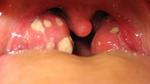

تعد اللوزتان اللتان تقعان في آخر الفم خطاً دفاعيّاً ضد مسببات المرض التي تدخل إلى الفم، أو عبر الأنف، فتقوم بمحاصرتها ومهاجتمها، ولكن في بعض الأحيان تصاب هي بهذه الميكروبات من فايروسات وبكتيريا، مما يؤدي إلى التهابها واحمرارها، ويكون الصديد عليها، وكذلك تكون رائحة نفس المريض كريهة، مع آلام في الحلق.

وينتشر مرض التهاب اللوزتين بين الأطفال في الغالب، إلا أنه يصيب البالغين أيضاً، كما أنه من الممكن تحوله إلى مرض مزمن، أي أن تلتهب اللوزتان كل فترة من الزمن، فيتم اللجوء لاستئصالهما، الأمر الذي يجعل الجسم أكثر عرضة للإصابة بالأمراض.